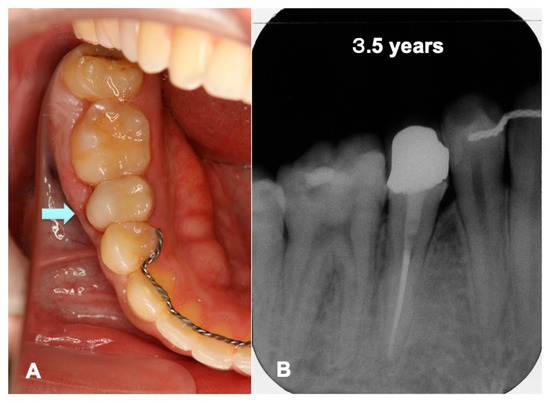

3.1. Gross View and Examinations after Surgery

3.2. Radiographic Evaluation